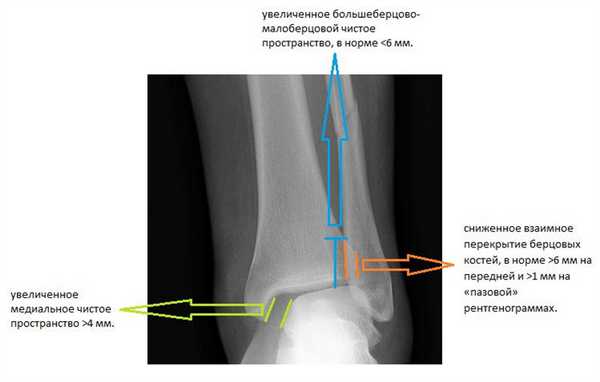

При детальном изучении снимков определяется увеличение межберцовой щели до 7,5 мм, уменьшения зоны перекрытия большеберцовой и малоберцовой костей до 5 мм, отсутствие на стороне поражения перекрытия тени таранной кости и малоберцовой кости.

На рентгенограмме костей правого и левого голеностопных суставов в прямой проекциии, снимки стоя - справа определяются признаки повреждения дистального межберцового синдесмоза - степень взаимного перекрытия берцовых костей 5мм (в норме больше 6мм) увеличенное большеберцовое - малоберцовое пространство - 7.5мм (в норме до 6мм).

Помимо тщательного сбора анамнеза, осмотра и функциональных тестов, важную роль в диагностике повреждений межберцового синдесмоза играют инструментальные методы. В первую очередь выполняются рентгенограммы в прямой и боковой проекции голени на протяжении, для исключения высоких переломов лодыжек.

Вторым важным моментом является выполнение снимков с выведением межберцового «паза» (проекция Mortise, 15-20° внутренней ротации голени).

Её информативность значительно возрастает при выполнении рентгенограмм с нагрузкой и одновременно обеих нижних конечностей. Помимо «пазовой» рентгенограммы в диагностически неоднозначных случаях выполняют стресс-рентгенограммы с наружной ротацией.

Признаками, указывающими на разрыв межберцового синдесмоза служат:

-сниженное взаимное перекрытие берцовых костей, в норме >6 мм на передней и >1 мм на «пазовой» рентгенограммах.

-увеличенное медиальное чистое пространство >4 мм.

-увеличенное большеберцово-малоберцовой чистое пространство, в норме